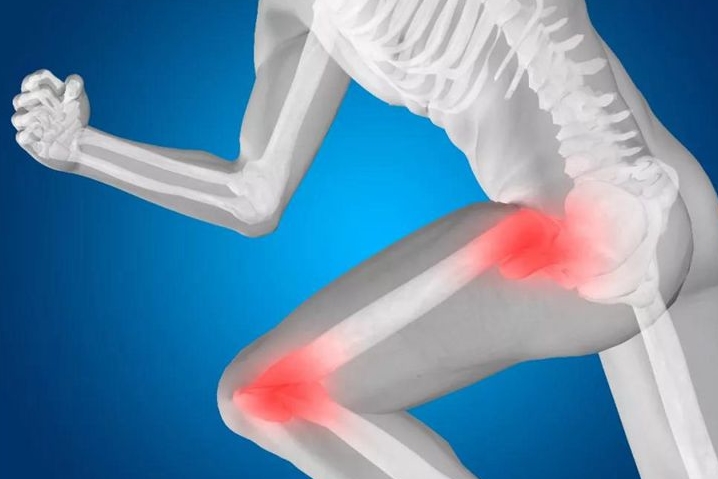

3238跑步伤膝盖?这件事更伤膝盖你却天天做

近年来不断有关于“日走万步伤膝盖”、“夜跑伤关节”的说法,很多人不敢过度运动,就怕伤了膝盖。美国《骨科与运动物理治疗杂志》曾发表一篇研究文章讲到:“健身跑的人们关节炎发生率仅3.5%,而选择静息生活方式、久坐不动人群的关节炎发生率却为10.2%,竞技体育的赛跑者的关节炎发生率13.3%”。结论是:久坐比跑步更伤膝。看到这个数据,是不是颇感意外?原来每天坐着刷微信,坐着看电视,坐着吃饭,坐着看报,坐...